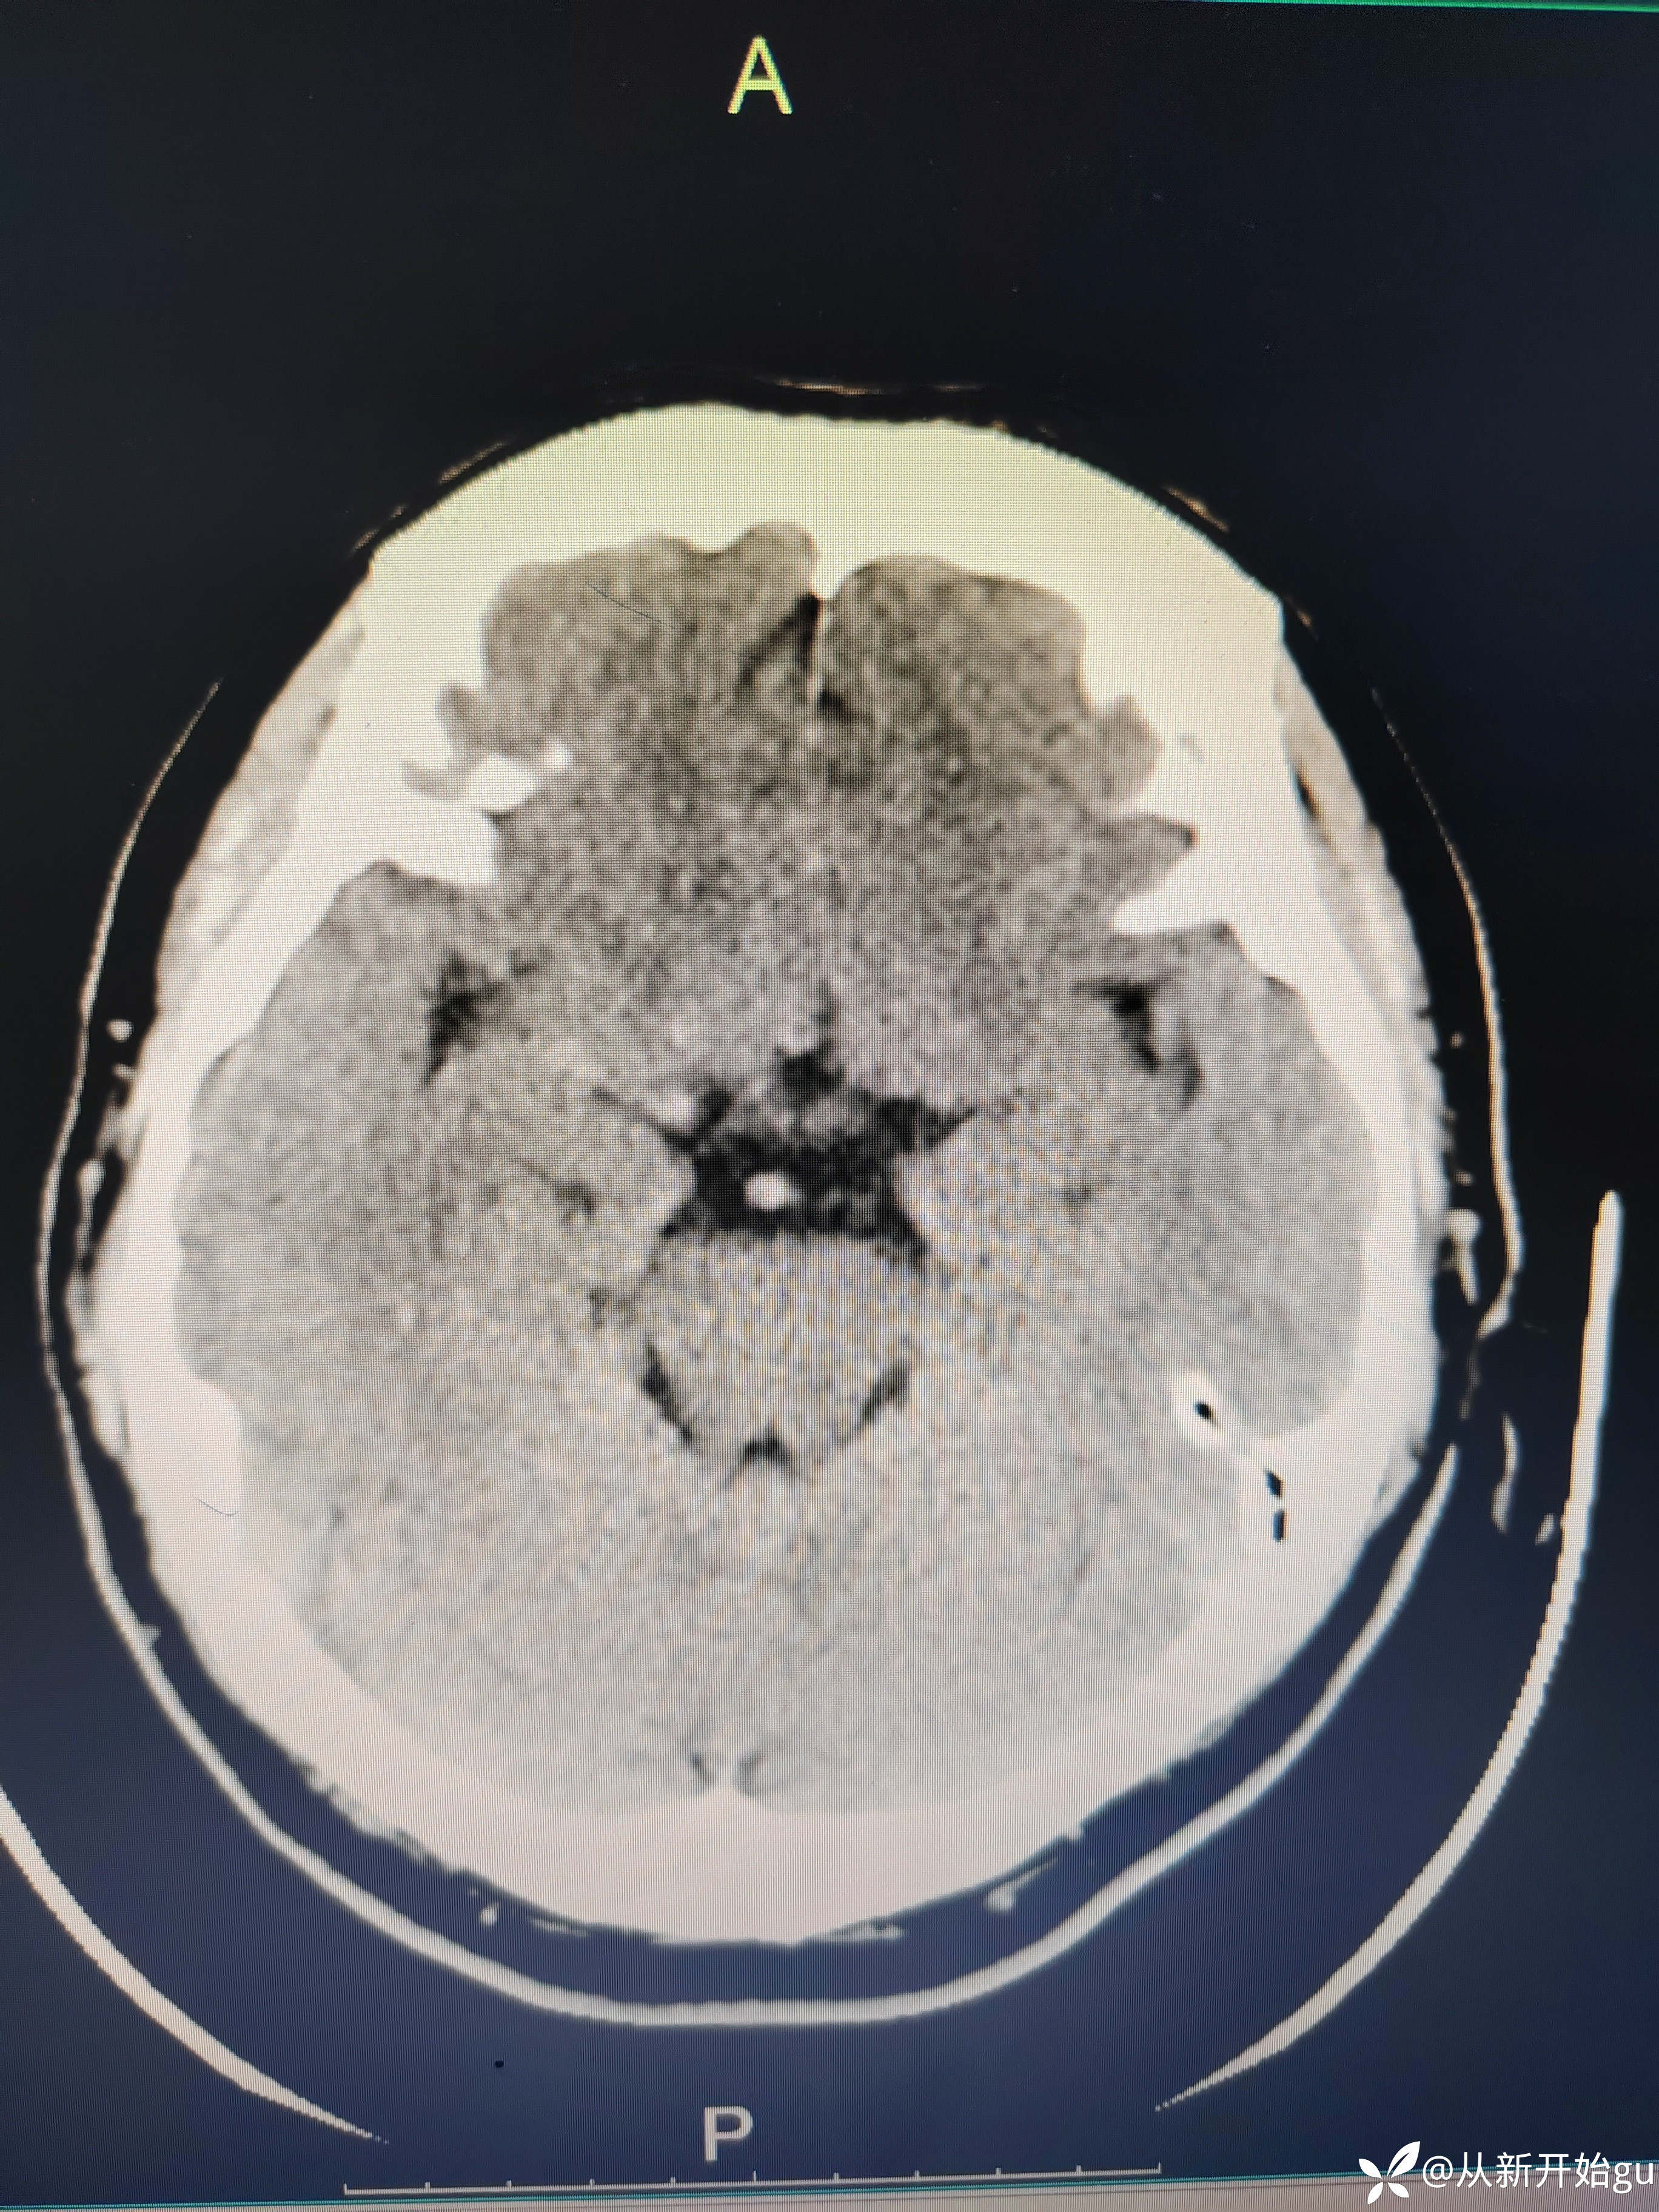

患者51岁男性,主因左下肢活动障碍1小时来院。既往高血压病史,查体,右侧鼻唇沟稍浅(家属诉之前就这样),神舌居中,左侧下肢肌力5级-,左侧跟膝胫试验欠稳准,左侧巴氏征阳性,评分也就一分,鼻唇沟稍浅未纳入。行颅脑CT检查如图所示

患者左下肢屈膝位—伸直过程中,左下肢费力感,左下肢僵硬感。常规我是会做个DWi明确一下,晚上都11点了(心疼放射科兄弟,就没做),直接和家属谈了一句溶栓,简要的说明,可溶可不溶,考虑病灶比较小(致残不致残都承担着同样的风险,个人不太想给溶)。家属比较积极,最后给予溶栓治疗。溶栓后无明显改善,第二天晨起诉明显减轻,但较正常下肢还是有区别。完善核磁检查(发病10小时做的)无新发梗死灶。血管如图所示: